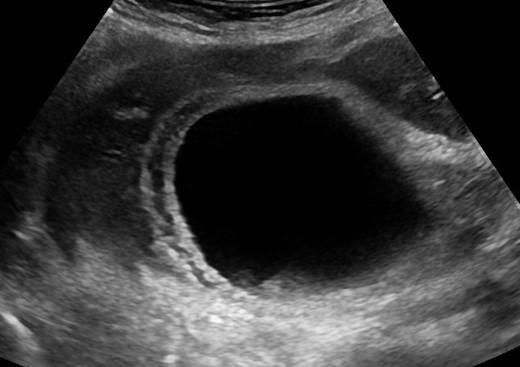

Viêm túi mật

Viêm túi mật - Ảnh 4

» Thông tin: Nữ giới – 88 tuổi.

» Lâm sàng: Đau mạn sườn phải / Sốt.